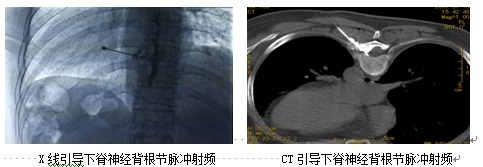

“如果神经阻滞有一定效果,但还没达到患者的预期目标,我们还可以针对神经进行脉冲射频调控治疗。”万丽说,治疗时,把射频针穿刺到病变神经周围,通过脉冲电刺激,对神经进行调控,减轻神经周围炎症,促进神经修复,从而缓解疼痛。